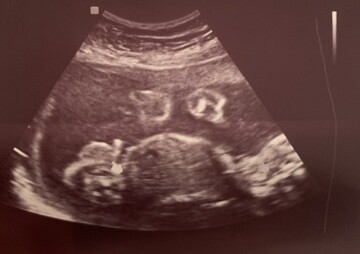

Dobry den, jdu k Vam s asi banalnim dotazem, tyka se pohlavi miminka do 21tt vsichni doktori na 99,9 procent me ujistovali, ze se jedna o divku a vcera jsem bohuzel mela neprijemny zazitek s panem doktorem na 2.velkem utz, kde mi ukazoval 40 minut holcici organy a pote mi mezi dverma rekl ze je to asi,,holka s pindikem” kdyz jsme se pana doktora 10 krat ptali s partnerem jestli tomma byt vtip nebo pravda pouze se smal a rekl, podivejte se na utu, bohuzel nejsem doktor a tento pan doktor na me i co se vysetreni tyka pusobil, ze je schopny mi tam vyfotir ruku a rict, ze je to chlapec...oba jsem s pritelem vysli z ordinace jako opareni a nastvani, ze nam pan doktor vlastne vzal radost z toho, ze dite je zdrave a dal nam brouka do hlavy.Celou noc jsem nespala nedela mi to moc dobre ani miminku tak bych chtela jen pro zajimavost zjistit jestli je pan doktor takovy srandista nebo pouze nevhodne oznamuje zpravy, dekuji

Dobrý den, na tuto otázku upřiměn nevím, jak odpovědět. Lékaře neznám a tudíž nejsem schopná odhadnout, zda vtikoval či nikoliv. Každopádně pohlaví je ve 20. týdnu již naprosto na 100% dobře přehledné, takže by každý lékař, který provádí specializovaný UZ měl být schopen říci, zda se jedná o kluka či děvče.